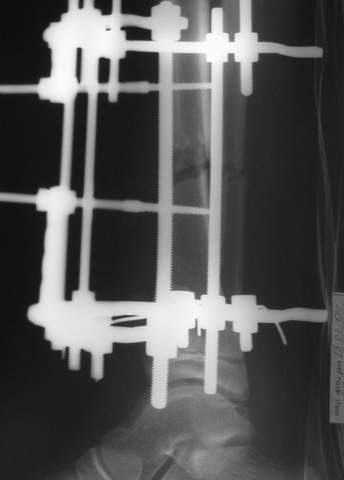

МТ мы используем, конечно, не только на голени. В прилагаемом примере у парня при поступлении была наружная ротация 40 гр. и "полумертвый" коленный сустав. Можно был бы, конечно, до конца использовать полную компоновку. Но для того он и есть метод выбора.

Всего наилучшего,